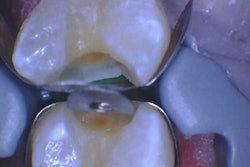

The oral surgeon ordered a cone-beam computed tomography (CBCT) scan. Below are the following images:

The oral surgeon consulted with an oral and maxillofacial radiologist who evaluated the images and provided an interpretation report. The following paragraph is from the report:

There is a large hypodense lesion (radiolucent), well defined and corticated, extending from the mesial aspect of tooth #17 to the periapical area of tooth #22. The lesion goes from the inferior cortex of the mandible to the alveolar ridge of teeth #18 and #19, the middle third of the root of tooth #20, and the apical third of the root of tooth #21. There is evidence of significant expansion in the coronal and axial projections. No calcifications are observed within the lesion. No periosteal reaction is observed (lingual or buccal). There is no radiographic evidence of perforation of the buccal or lingual walls of the lesion.

There is no radiographic evidence of root resorption or teeth displacement associated with the lesion. No gross caries is present in the teeth involved in the lesion. The inferior alveolar canal is well visualized and displaced buccally-apically by the lesion.

A few weeks later, the oral surgeon performed an incisional biopsy. The histopathology report was available a few days later. The following remarks are from the histology report:

The microscopic examination reveals a cystic lesion mainly lined by a thin layer of nonkeratinizing stratified squamous epithelium. There is minimal inflammation in the thick fibrous connective tissue wall. Invading epithelium demonstrates a basal layer of columnar cells with hyperchromatic nuclei that shows reverse polarity and basilar cytoplasmic vacuolization. Suprabasal epithelial cells are loosely cohesive, resembling stellate reticulum.